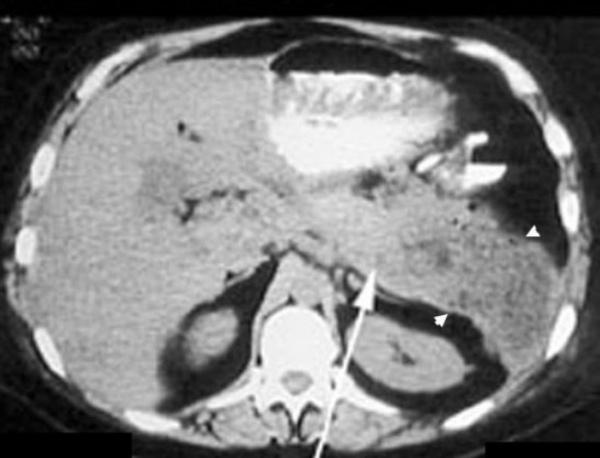

- Визуализирующие методики. УЗИ поджелудочной железы, КТ органов брюшной полости позволит определиться с локализацией и размерами очага, количеством абсцессов. При необходимости возможно одновременное проведение чрескожной пункции с аспирацией, исследованием и посевом содержимого.

КТ органов брюшной полости. Диффузно увеличенная поджелудочная железа. Большая стрелка указывает на тело поджелудочной железы, маленькие стрелки - на абсцесс, расположенный в хвосте поджелудочной железы.